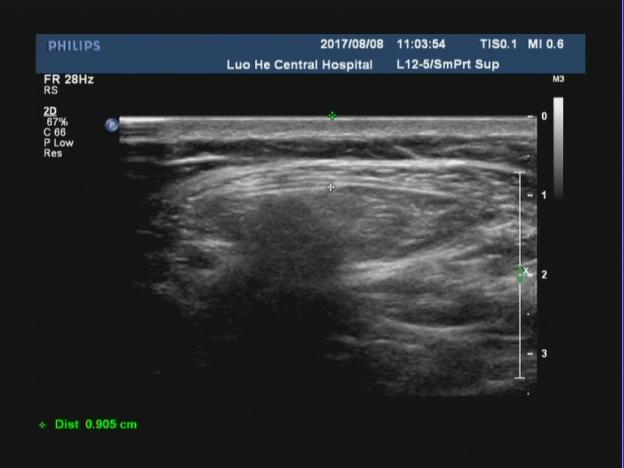

中年男性患者,腹部可见一巨大包块,位于开腹手术瘢痕处,从声像图上可以看出来,该包块直接位于腹部的皮下软组织后方,无肌肉层覆盖,而包块边界处可见肌肉层回声,并且包块内可见腹腔肠管回声,考虑符合腹壁的。

腹壁切口疝指临床体检可触及或影像学检查可显示的原手术切口下的腹壁缺损,是腹部外科手术后的常见并发症,常发生于年老体弱患者可伴或不伴腹壁包块,发病率通常为2%~11%。切口疝无法自愈,可引起患者不适或导致腹腔内容物绞窄。二维超声可直观了解疝环的大小、形态及深度,疝囊大小、位置,疝内容物及疝囊疝出和回纳途径。

对于切口疝二维超声扫描不仅能够清晰显示自皮肤表层到腹壁深层的解剖学全貌,还可直观显示切疝环的大 小、形态及深度,疝囊大小、位置及疝内容物。通过嘱患者用力咳嗽增加腹压或改变体位等方法,超声可实时动态显示疝囊由筋膜缺损处疝出以及回纳的过程。但随着腹壁外科的不断进展和疝修补技术的多样化,外科医师术前需要了解更具体的信息。以往研究认为二维灰阶超声可以检出所有切口疝。但当切口疝的缺损范围较大或存在多发性切口疝时,受小器官探头长度限制,二维灰阶超声存在测量数据明显偏小和病灶检出率明显降低等问题。因此我们可以采用现在新机器上的宽景成像技术,通过连续扫描与拼接图像,不仅可以在同一幅图像上显示较大范围的病灶并进行测量,还可显示周围相邻组织的情况。因此我们要会用、善用新软件,宽景成像不仅可对腹壁切口疝进行容积扫描,明显提高疝气病灶的检出率,客观显示整个切口疝的全貌,准确测量疝囊的大小,为临床医师对切口疝的分类提供准确数据;还可以显示二维超声所不能显示的冠状面图像,更准确地测量疝环,为临床医师选择疝修补术手术方式和决定补片大小提供具体精确的数据。